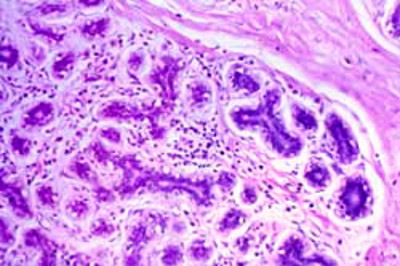

An activated stem cell signature as a biomarker to predict malignant progression of DCIS PI: Jay Desgrosellier, University of California, San Diego Ductal carcinoma in situ (DCIS) is the most commonly diagnosed pre-malignant lesion in the breast. Only about half of these cases will progress to invasive breast cancer, yet many women with DCIS needlessly undergo aggressive treatment. To better understand which cases of DCIS are likely to become invasive, researchers studied whether an activated stem cell signature will identify DCIS lesions that are likely to progress to invasive breast cancer, in hopes of reducing unnecessary treatment. One of their most exciting discoveries was a specific type of cancer cell marked by a protein called RSAD2 (also known as Viperin). These RSAD2+ cells have stem-like properties, respond to immune signals, and are found more often in invasive cancers than in DCIS. The team also found that these cells can attract immune cells that actually help tumors grow and push neighboring cancer cells toward a more aggressive state. These findings suggest that RSAD2+ cells may play a central role in the shift from non-invasive to invasive cancer. The study generated 5 publications, including a report in Frontiers in Cell and Developmental Biology. |